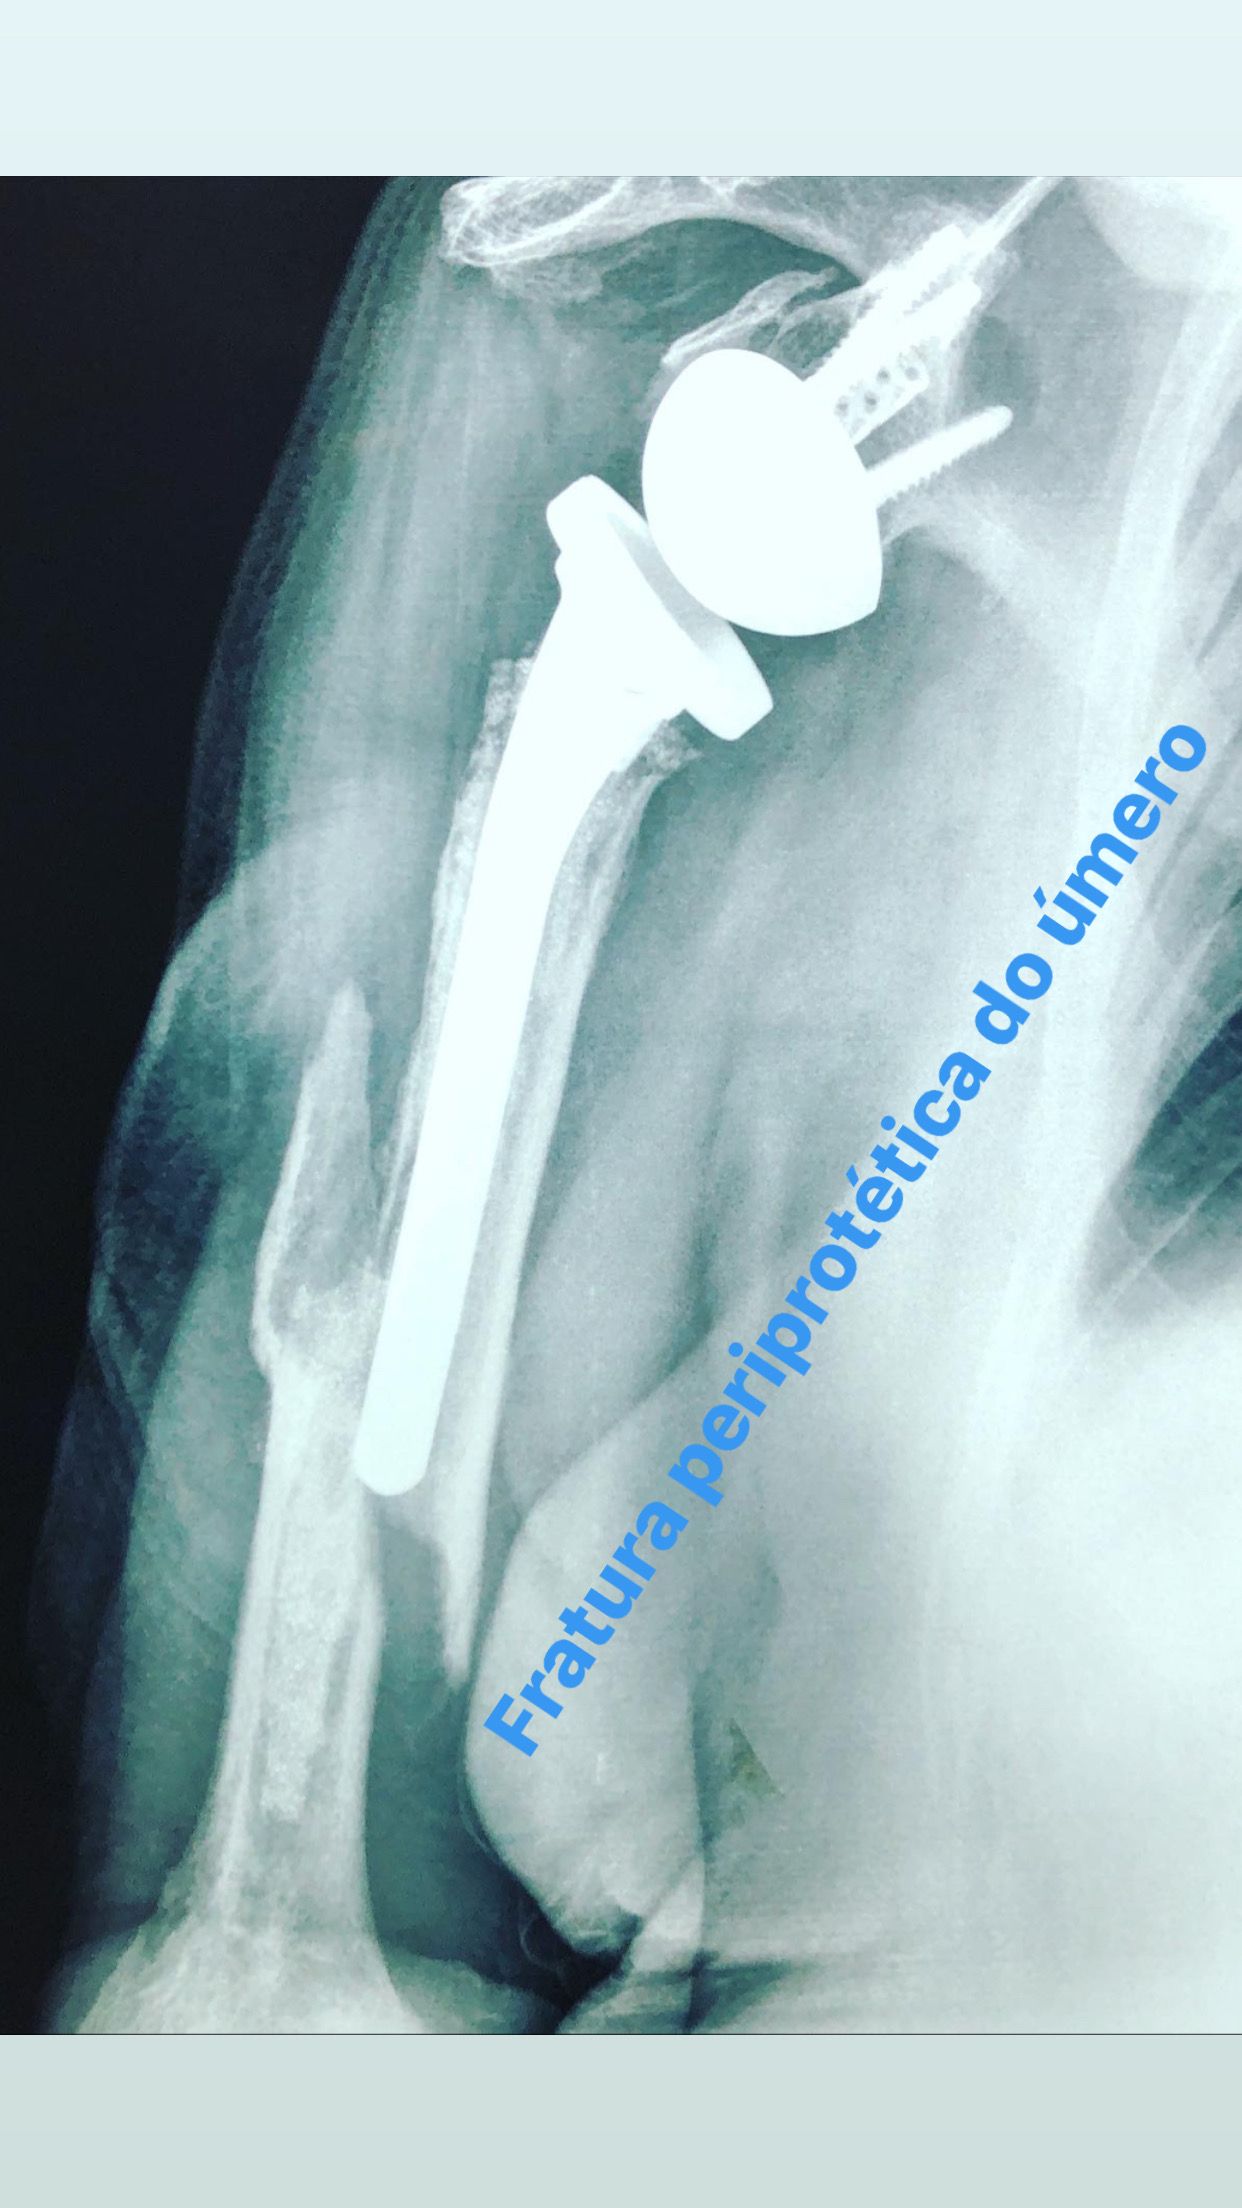

•Grande experiência em artroplastias(próteses) primárias e de revisão de joelho e ombro;

Se você tem percebido uma diminuição da força do ombro, dificuldade para movimentá-lo ou carregar objetos, além de dores que podem irradiar desde a região escapular, para o braço ou para a região do pescoço, fique atento! Podem ser sintomas da lesão do manguito rotador. O manguito rotador é uma estrutura que envolve a cabeça do úmero, parte superior do osso do braço, que se articula à escápula. Sendo responsável pela estabilidade articular do ombro e pelos movimentos desta área. Essas lesões podem acometer pessoas de diferentes idades. As principais causas são: a degeneração dos tendões pelo avanço da idade, o esforço repetitivo com impacto articular, e os traumas.

Lesão de manguito rotador